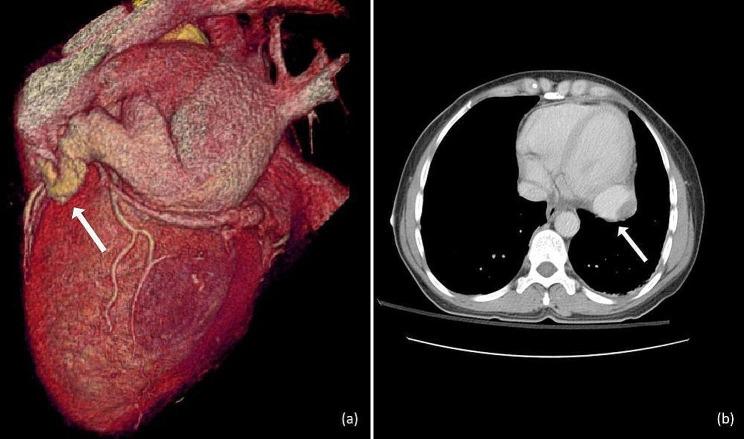

We describe the case of a 46-year-old woman with non-ST-elevation myocardial infarction (NSTEMI) caused by a "giant" CAA. Various imaging modalities revealed a thrombus-containing aneurysm located at the right-posterior cardiac border, with established arteriovenous communication with the distal part of left circumflex artery (LCx). After initial treatment with dual antiplatelet therapy, a relapse of pain was reported along with a new increase in troponin levels, electrocardiographic abnormalities, reduced left ventricular ejection fraction (LVEF) and thrombus enlargement. Surgical excision of the aneurysm was favored, revealing its true size of 6 cm in diameter. Τhe aneurysm was excised without complications. The patient remained asymptomatic during follow-up.

我们描述了一例 46 岁女性因“巨大”CAA 导致非 ST 段抬高型心肌梗死(NSTEMI)的病例。各种影像学检查显示位于心后缘右侧的血栓性动脉瘤,与左回旋支(LCx)远端有明确的动静脉交通。初始双联抗血小板治疗后,报告胸痛复发,肌钙蛋白水平再次升高,心电图异常,左心室射血分数(LVEF)降低,血栓增大。倾向于手术切除动脉瘤,显示其真实大小为 6cm 直径。动脉瘤切除无并发症。患者在随访期间无症状。